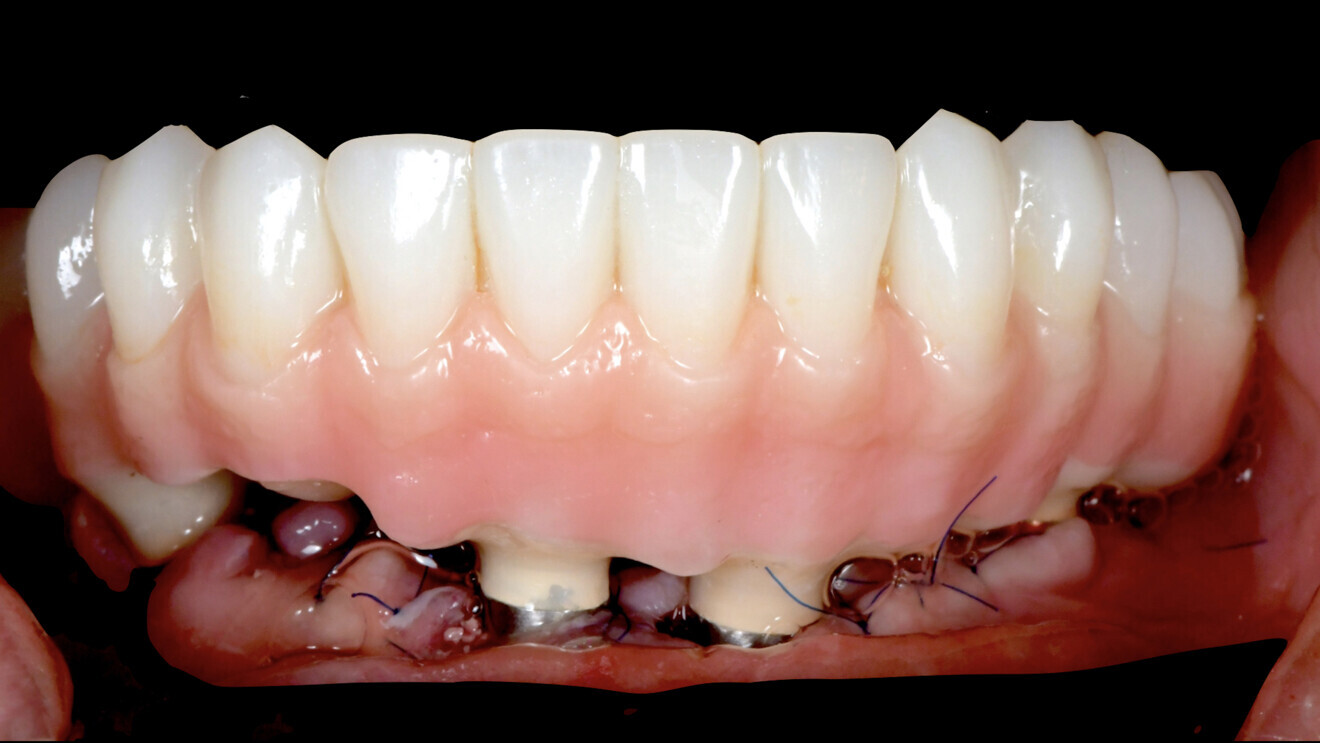

Le projet prothétique (validé préalablement en bouche) peut être aussi numérisé en fichier STP et, dès lors, il peut être combiné avec le fichier STL de la situation initiale. Cela permet de faire apparaître le projet prothétique sur les données osseuses : la planification est alors plus fonctionnelle et biologique. Dans le même temps, il est possible de transformer ce projet prothétique en prothèse provisoire (logiciel DTX Lab) adapté à la planification (perforation de la prothèse en regard de la position des futurs implants et piliers). Cette prothèse comporte également quatre tiges au niveau de l’intrados, dessinées en regard de zones osseuses. Après forage guidé par la navigation, elles permettent de positionner la prothèse correctement (Fig. 7). La prothèse provisoire a été préparée en PMMA et réalisée avec une résine composite rose pour simuler la gencive (Fig. 8).

La prothèse provisoire est présentée en face des piliers provisoires puis elle est positionnée précisément grâce aux tiges qui seront réceptionnées par les logements intra-osseux réalisés par la navigation, assurant donc leur précision de positionnement. Il est alors possible d’injecter le composite Flow pour joindre les piliers provisoires et la prothèse provisoire (Fig. 12). Après adjonction et finition du composite injecté par polissage, la prothèse provisoire peut être vissée pour toute la durée de la phase d’ostéo-intégration (Fig. 13). Une radiographie réalisée après la mise en place de la prothèse provisoire a montré une bonne intégration des implants (Fig. 14).